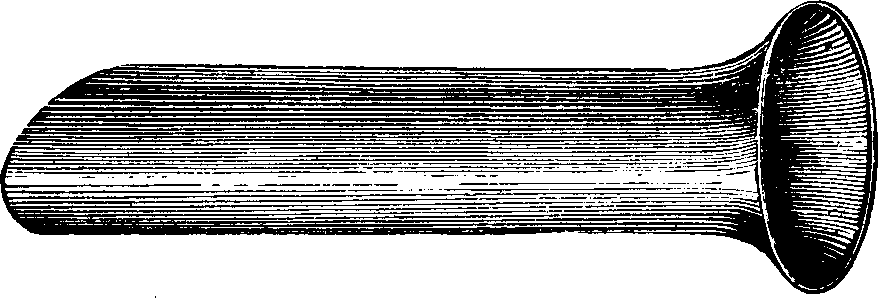

Fig. 3. THE UTERINE DILATOR. This instrument is introduced

into the canal of the uterine neck with its blades closed. By means of the

thumb-screw the blades are then separated as shown in this illustration,

the cervical canal being thereby dilated to the required extent.

Treatment. From the nature of this malady, it will readily be seen that no medical treatment can effect a radical cure. We must therefore resort to surgery. In a small proportion of cases, the stricture may be cured by repeated dilations of the constricted part of the cervical canal. This may be accomplished by using a very smooth probe which is fine at the point, but increases in size, so that its introduction will widen and expand the orifice and canal. The stricture may be overcome in many cases by using different sized probes. In some instances, we have employed the uterine dilator, represented by Fig. 3. We have also introduced sea-tangle and sponge tents into the neck of the womb, and allowed them to remain until they expanded by absorbing moisture from the surrounding tissues. The latter process is simple, and in many cases preferable. By means of a speculum (see Figs. 15 and 16), the mouth of the womb is brought into view, and the surgeon seizes a small tent with a pair of forceps and gently presses it into the neck of the womb, where it is left to expand and thus dilate the passage. If there seems to be a persistent disposition of the circular fibers of the cervix to contract, and thus close the canal, a surgical operation will be necessary to insure permanent relief. In performing this operation, we use a cutting instrument called the hysterotome (see Figs. 4 and 5). By the use of this instrument, the cervical canal is enlarged by an incision on either side. The operation is but slightly painful, and, in the hands of a competent surgeon, is perfectly safe. We have operated in a very large number of cases and have never known any alarming or dangerous symptoms to result. After the incision, a small roll of cotton, thoroughly saturated with glycerine, is applied to the incised parts, and a larger roll is introduced into the vagina. The second day after the operation, the cotton is removed, the edges of the wound separated by a uterine sound or probe, and a cotton tent introduced into the cervix, and allowed to remain, so that it will expand and thus open the wound to its full extent. This treatment must be thoroughly applied, and repeated every alternate day, until the incised parts are perfectly healed.